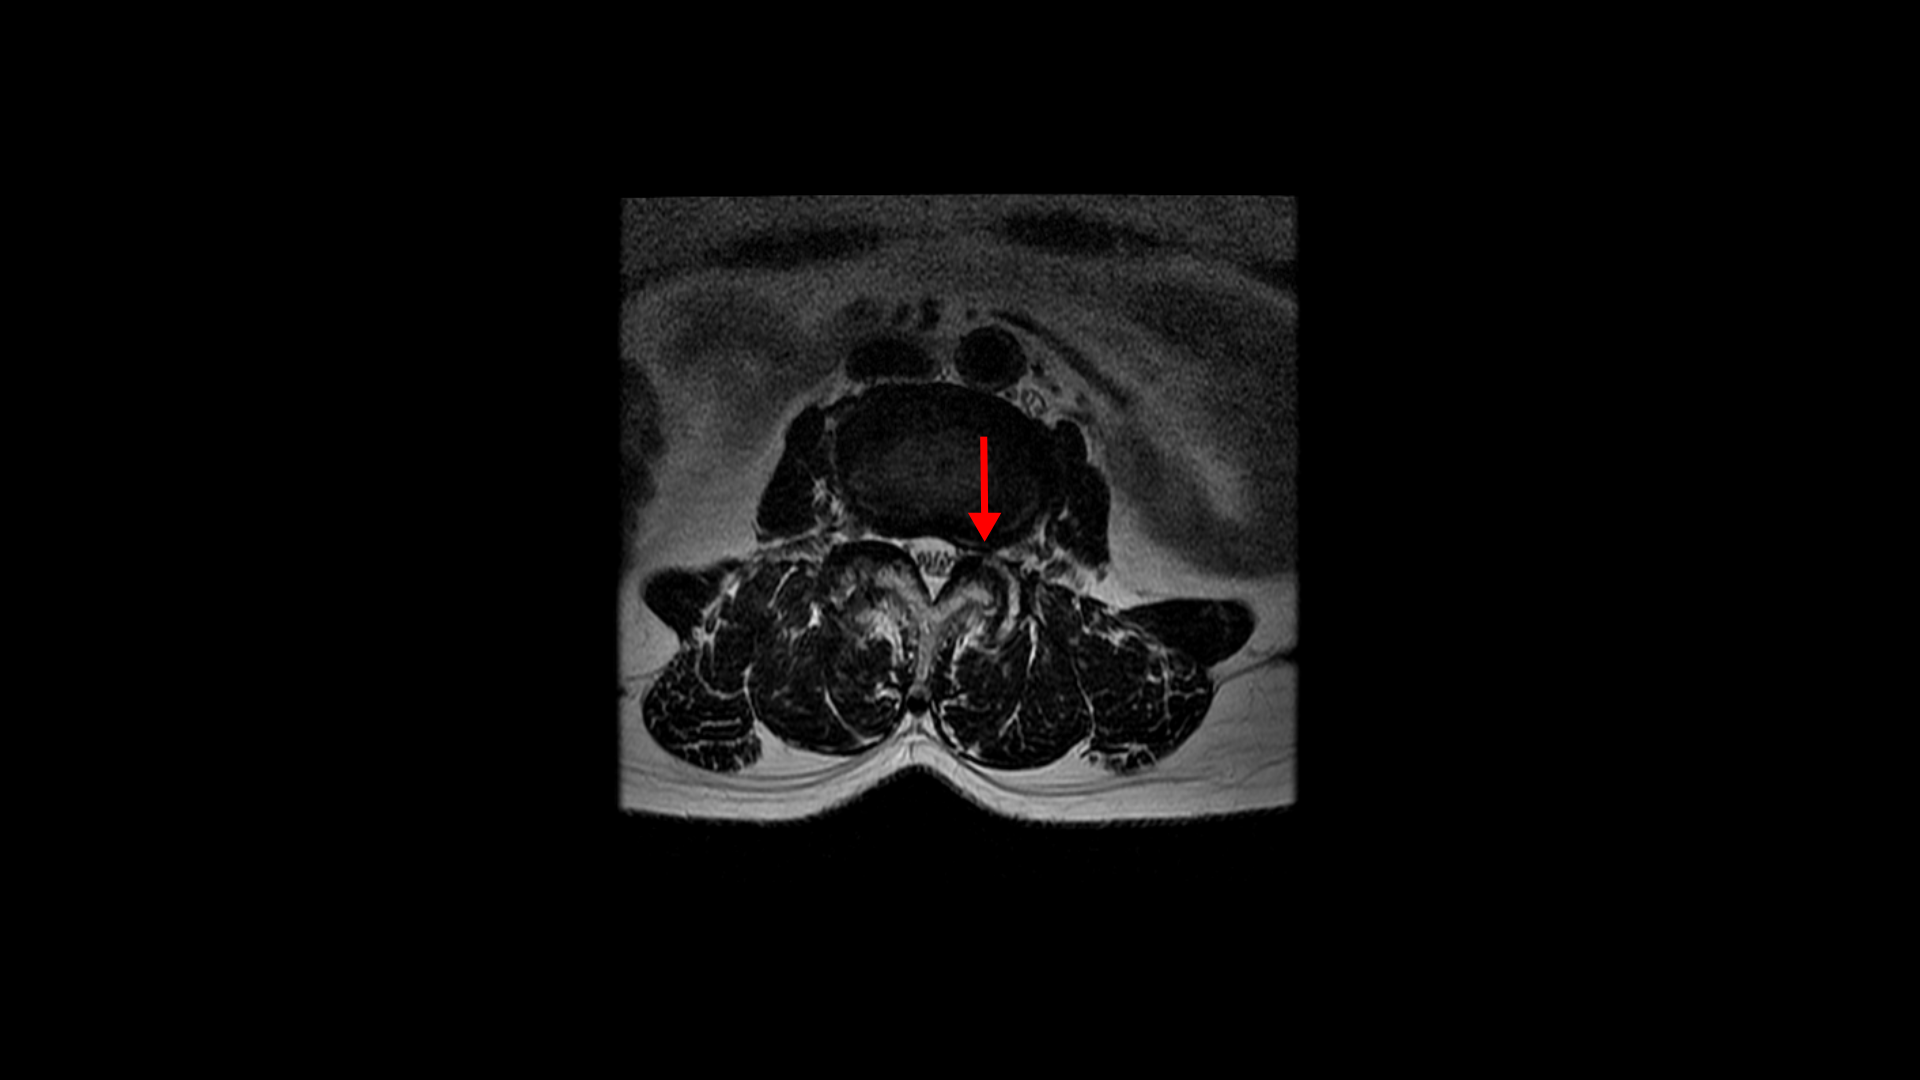

우선 이 환자분의 MRI를 함께 보겠습니다. 이 환자분의 척추에는 3번 4번과 4번 5번에 각각 1단계의 전방전위증이 있습니다.

3번 4번에는 왼쪽으로 디스크 탈출이 있고

중심성 협착도 있습니다.

그리고 4번 5번에도 왼쪽으로 퇴행성디스크와 후관절의 퇴행으로 신경 가지가 나가는 구멍이 좁아져 있습니다.

그리고 중심성 협착도 있습니다.

그런데 이 환자분의 제일 불편한 증상은 왼쪽이 아니고 오른쪽 엉치와 다리 증상입니다. 이분 오른쪽 신경 구멍들을 보면 전부 다 넓게 잘 열려 있습니다.

엉치와 다리 방사통을 일으킬만한 특별한 신경 눌림이 보이지 않는 것입니다. 그럼에도 불구하고 여러 마디의 전방전위증과 척추관 협착 그리고 디스크 탈출이 있으니까 그것을 원인으로 보고 신경 주사도 맞고 시술도 받으셨습니다. 그러나 별 효과는 없었습니다. 그리고 대학병원에서도 결국은 수술밖에 방법이 없다고 수술을 권유하였습니다.